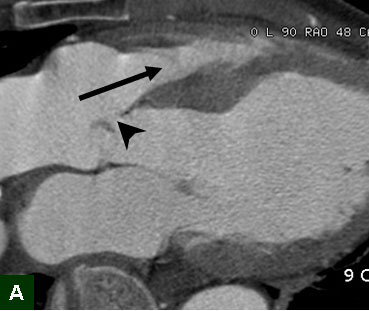

Kawasaki disease

Cherry Kim, Korea University Ansan Hospital